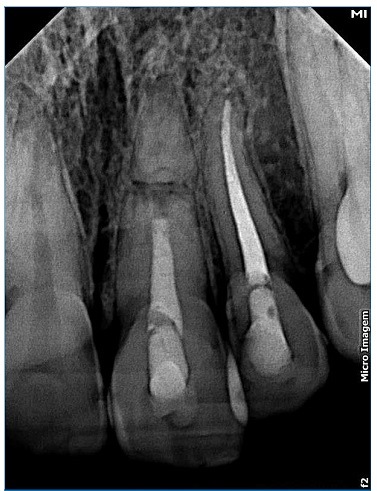

A 15‑year‑old Caucasian female patient was admitted to a private clinic 30 minutes after suffering a severe impact to the oral region during a basketball game at school in 2010. She was not wearing a mouthguard at the moment of the trauma. The intraoral examination revealed a cut on the lower lip and heavy bleeding in the maxilla’s anterior region (Figure 1). Besides, both teeth 21’s (left maxillary central incisor) and 22’s (left maxillary lateral incisor) crowns were slightly dislocated in a palatal and coronal direction, and tooth 21 had an enamel fracture (Figure 2). The patient had vital signs within the normal range and did not have any systemic alterations. Radiographic examination revealed a horizontal root fracture in the middle third of tooth 21 and an enlargement of the periodontal space of tooth 22 (Figure 3). Teeth 21 and 22 did not respond to the cold test with Endo Ice (Maquira, Maringa/PR, Brazil), while the response from teeth 12 (right maxillary lateral incisor), 11 (right maxillary central incisor), and 23 (left maxillary canine) was compatible with a normal pulp. The patient reported pain during the percussion exam on all teeth involved.

Figure 3 Radiographic aspects at the emergency care: root fracture of tooth 21 and tooth 22’s extrusion

Clinical and radiographic follow‑ups were performed after 6 months, and then 3, 7, 8, 9, and 10 years. In the 10‑year control, the patient remained asymptomatic. Her teeth 11, 12, and 23 continued to respond positively to the sensitivity tests and seemed to be in function (Figure 5). Root fracture’s consolidation with rounding of the fracture edges, calcification of the apical third, bone formation between the fragments, and absence of periapical lesion or root resorption were noted radiographically (Figure 6). Moreover, the obturation paste of calcium hydroxide associated with 2% chlorhexidine gel and zinc oxide was still filling the root canal of teeth 21 after ten years.

IADT recommends endodontic treatment for traumatized teeth to avoid root resorption if pulp necrosis is detected.12 In this study, the patient’s tooth 21 was diagnosed with pulp necrosis 14 days after the trauma due to not responding to sensitivity tests. The patient also presented painful symptoms. The preponderance of pulp necrosis in the coronary fragment after root fractures is about 20%, while the apical fragment remains vital in most cases.25 Thus, tooth 21 was treated endodontically up to the root fracture line12 and filled only with an obturation paste composed of calcium hydroxide P.A., 2% chlorhexidine, and zinc oxide.16 This paste has antibacterial properties;26 is biocompatible,27 and acts as a physical barrier, helping seal root canals.28 It was originally proposed as a treatment for avulsed teeth but currently is equally used in the apexification of teeth with open apex28,30,31and the treatment of horizontal root fractures, with satisfactory results.16,29,32 That paste is used as a filling material in root fractures due to inducing the formation of a mineralized barrier,28,31 which was observed during this case’s radiographic follow‑up with roundness of the fracture edges and bone formation between the fragments. These findings are similar to those obtained by other authors33,34who filled the root canal of fractured roots with MTA. However, unlike in Yildrim and Gencoğlu’s study,33 no coronary darkening was observed in this case report. In addition, like in another case,34 the obturation paste used in this study was still filling the root canal after 10 years.